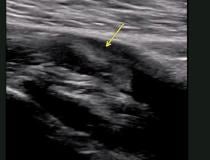

This photo gallery shows the variety of radiological presentations of COVID-19 (SARS-CoV-2) in medical imaging, including computed tomography (CT), radiograph X-rays, ultrasound, echocardiograms and magnetic resonance imaging (MRI). The radiology images show examples of typical COVID pneumonia in the lungs and the numerous complications the virus causes in the body in multiple organs, including the brain, kidneys, heart, abdomen and vascular system.

Ultrasound, especially hand-held ultrasound imaging devices, have become a primary imaging modality for novel coronavirus because of the ease to bag the device and sterilize it after use. CT and mobile X-ray systems are also used as front-line imaging systems for COVID-positive or suspected COVID patients.